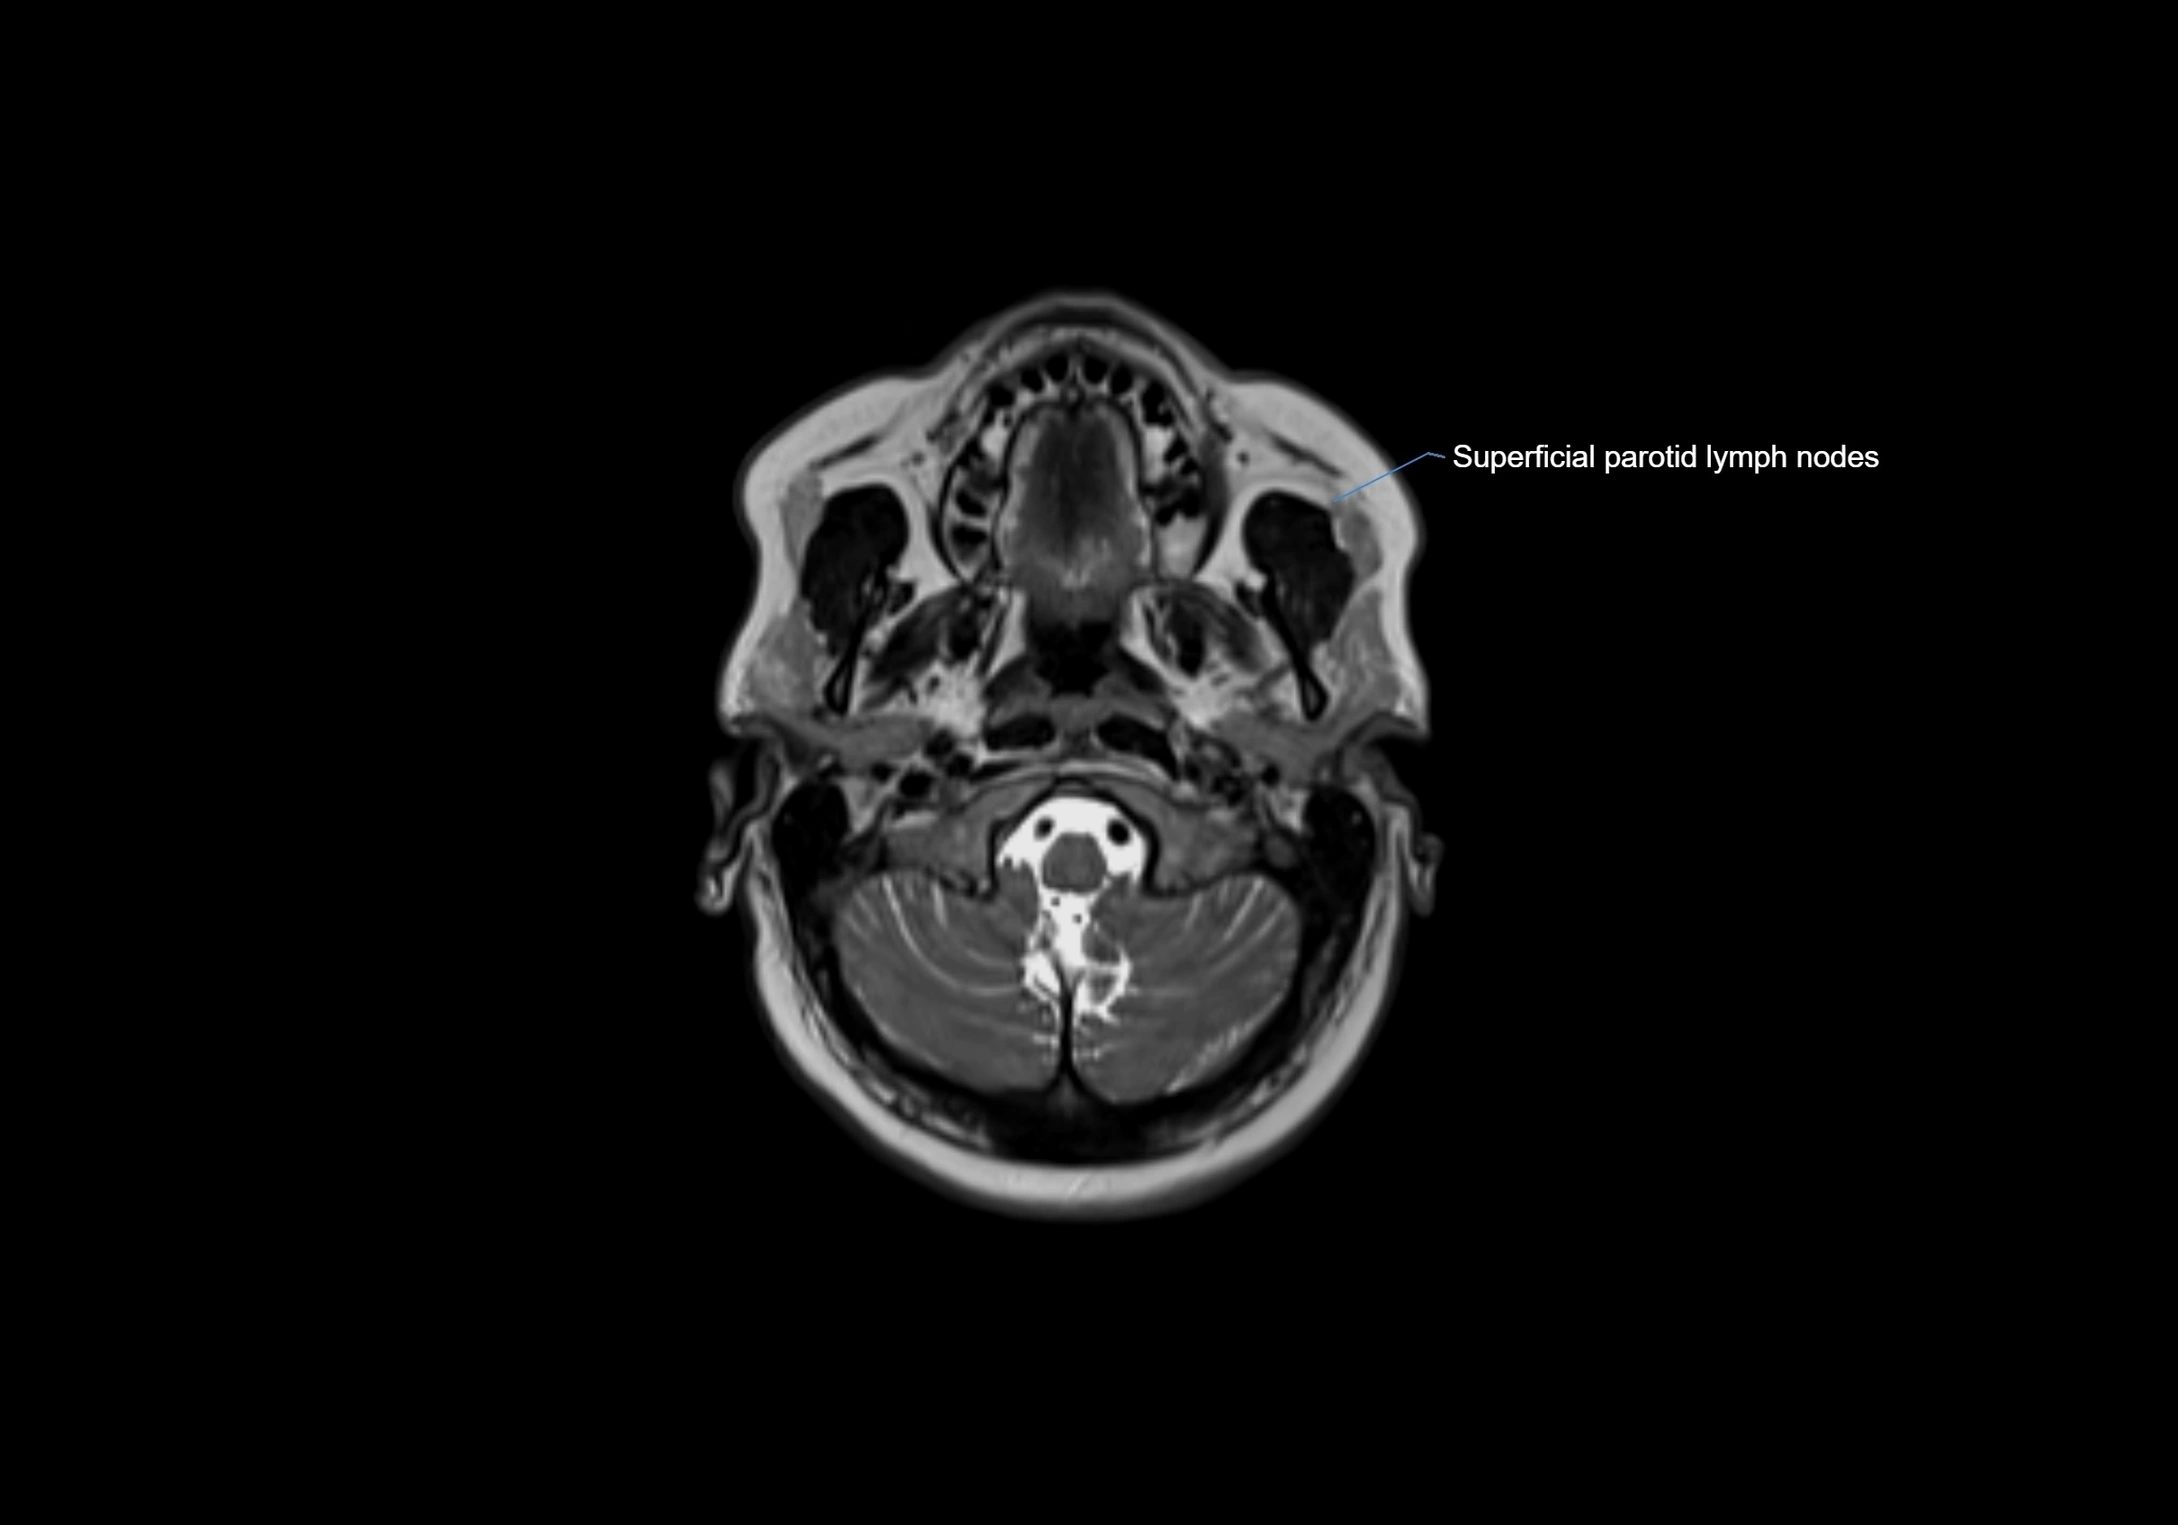

Accessory lymph nodes are small, secondary lymph nodes located along the main facial and cervical lymphatic chains, often adjacent to primary lymph nodes, such as preauricular, submandibular, or occipital nodes. They are typically less than 5 mm in diameter, embedded within subcutaneous fat or connective tissue, and may be variable in number and location. These nodes provide additional filtration and immune surveillance for lymph collected from the face, scalp, and neck regions. Accessory lymph nodes are usually non-palpable in healthy individuals but may enlarge in response to infection, inflammation, or metastasis, making them clinically significant.

Location

• Found along primary lymph node chains, including preauricular, submandibular, parotid, and occipital regions

• Embedded in subcutaneous fat or superficial fascia, often lateral or posterior to primary nodes

MRI Appearance

T1 Post-Contrast (Gadolinium-enhanced):

• Normal nodes may show mild, homogeneous enhancement

• Inflamed or metastatic nodes demonstrate marked homogeneous or heterogeneous enhancement, highlighting the cortex and fatty hilum

• Post-contrast imaging helps detect early metastasis, infection, or inflammatory changes